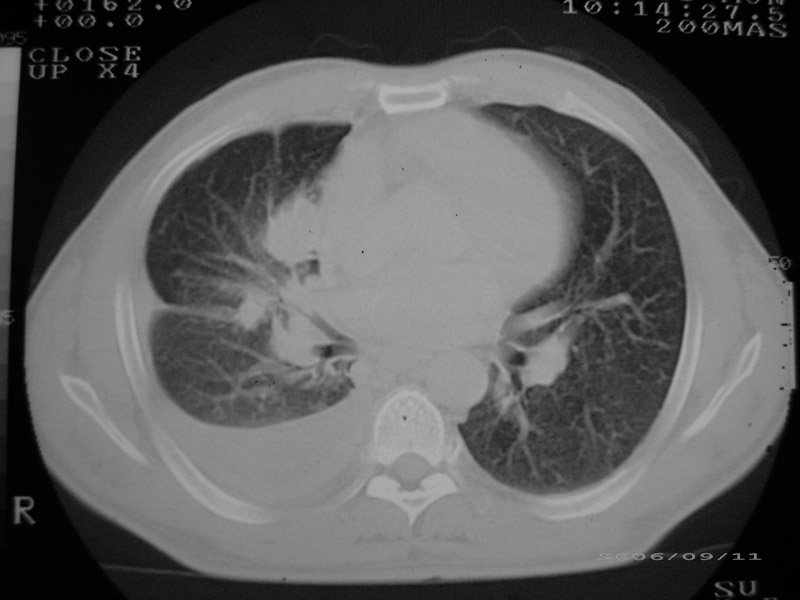

以下是引用守望可可西里在2006-9-11 15:29:00的发言:[br][br] ct平扫表现:右侧胸膜腔缩小,积液,胸膜增厚且不均匀、不规则,以纵隔胸膜增厚为主,边缘呈锯齿状,并见附壁内突之结节状肿块影。右肺含气量减少,纹理聚集,右肺门中下部见数个肿大的淋巴结。纵隔无移位,内未见明显肿大淋巴结,双侧主支气管以及各叶、段支气管比较通畅。。[br] 考虑:右侧胸膜恶性间皮瘤,伴肺门淋巴结转移。